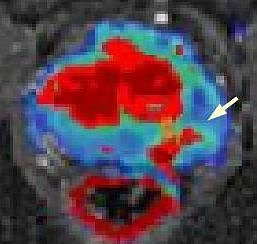

MRT von Prostata (Foto: SHK)

Bei diesem Jahrestreffen der nordamerikanische Röntgengesellschaft, an dem 65.000 Fachleute teilnehmen, wird der Nordhäuser Mediziner über die MR-gestützte Abklärung von auffälligen Befunden an der Prostata referieren. Das Nordhäuser Krankenhaus ist eines von sehr wenigen Häusern in Deutschland und bislang das einzige in Thüringen, das diese interventionelle Methode anbietet (siehe Foto, Pfleil zeigt auf Karzinom). In diesem Zusammenhang besteht seit längerem eine enge Zusammenarbeit mit dem Fraunhofer-Institut in Bremen. Wenn bei einem Tumorverdacht die ultraschallgestützte Biopsie der Prostata keinen Tumornachweis erbringt, kann die MRT-basierte Biopsie als zweite Option angewandt werden. Der Vortrag befaßt sich mit den nötigen Vorbereitungen und der benötigten Hardware, der Planung der Biopsie, der Durchführung, möglichen Komplikationen und den histologischen Ergebnissen im Vergleich zu den ursprünglichen Bildcharakteristika im MRT.

Hierbei hat sich eine Kooperation mit niedergelassenen urologischen Kollegen in Nordthüringen und Sachsen-Anhalt herausgebildet, die folgerichtig auch Koautoren dieses Vortrags sind. Die MR-gestützte Biopsie ist vom Nordhäuser radiologischen Team inzwischen bei mehr als 50 Patienten im Südharz-Krankenhaus bereits erfolgreich angewandt worden und daraus konnten Erkenntnisse für die weitere Arbeit gewonnen werden, die nun vorgestellt werden.